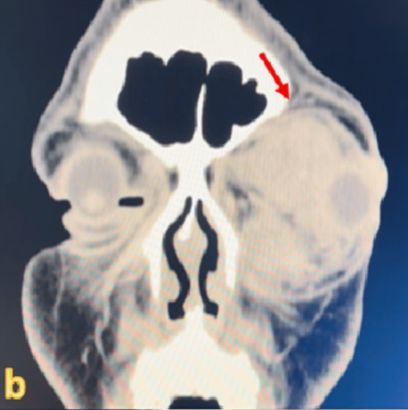

CT 촬영 결과, 시신경을 심하게 누르고 있는 큰 종양이 발견됐다. 이후 제거 수술을 받았으나, 이미 손상된 시신경은 회복되지 않았다.

두 번째 사례 환자는 42세 여성이다. 최근 3개월간 오른쪽 눈이 붓고, 사물이 두 겹으로 보이는 증상이 나타났다. 마찬가지로 CT 검사에서 종양이 확인됐고, 즉시 제거 수술을 받았다.